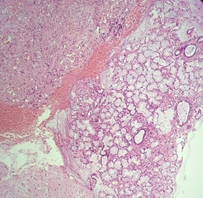

A 55-year-old female presented with a swelling over the hard palate for the last 2 months. It was not associated with pain or difficulty in chewing. On examination, there was swelling over the hard palate around 2X2 cm in dimension, tender to touch on deep palpation, soft, cystic, and compressible. There was no discharge on palpation from the swelling. Dental hygiene was poor and carious teeth were also there. She had a history of coronary angioplasty a few years back and she was on regular follow-up there. CECT neck was suggestive of infective? periapical cyst/ abscess formation along the hard palate in the midline extending into the right superior alveolar process at the roof of the right lateral incisor (Figure 1).

Figure 1 Coronal and sagittal.

CECT PNS (neck also) revealed a well-defined mild peripherally enhancing hypodense area along the hard palate in the midline extending into the right superior alveolar process at the roof of the right lateral incisor with adjacent cortical irregularity and erosion possibly infective etiology?/periapical cyst/abscess formation. The patient was planned for Incision and drainage (curettage, if needed) under general anesthesia. A ‘U’ shaped incision (Figure 2) was given over the swelling and the irregular mass so found was removed and sent for HPE. Surrounding unhealthy tissue was curetted and suturing was done. The postoperative period was uneventful. Histopathological examination was suggestive of periapical granuloma (Figure 3a, 3b, 3c).